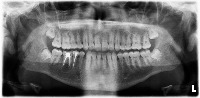

tooth-disease Computer Vision Project

graduation project

Classes (58)

Apical Lesion

Apical lesion

Artifical crown

Braces

Buccoangular Impacted tooth

Calculus

Canal obliteration

Class 1 cavity filling

Class 2 cavity filling

Class 3 cavity filling

Class 4 cavity filling

Class 5 cavity filling

Convergent root

Cystic lesion

Decidious teeth

Dilaserasgon

Distoangular Impacted tooth

Divergent root

Endodontically treated teeth

External Object

External resorption

Filling

Fractured crown

Furcation lesion

Germ

Horizontal Impacted tooth

Horizontal bone loss

Hypercementosis

Impacted tooth

Implant

Internal resorption

Inverted Impacted tooth

Lack of interproximal tooth contact

Lesion

Mesioangular Impacted tooth

Microdontic tooth

Open Apex

Open margin

Overeruption

Overhang

Periodontal bone loss

Pontic

Post

Post-Core Restorasyon

Prepared tooth

Pulp stone

Retainer

Root Root fracture

Signs of bone structure disorder

Signs of caries

Signs of secondary caries

Socket Supernumerary tooth

Vertical Impacted tooth

Vertical bone loss

Yeterli canal filling

Yetersiz canal filling